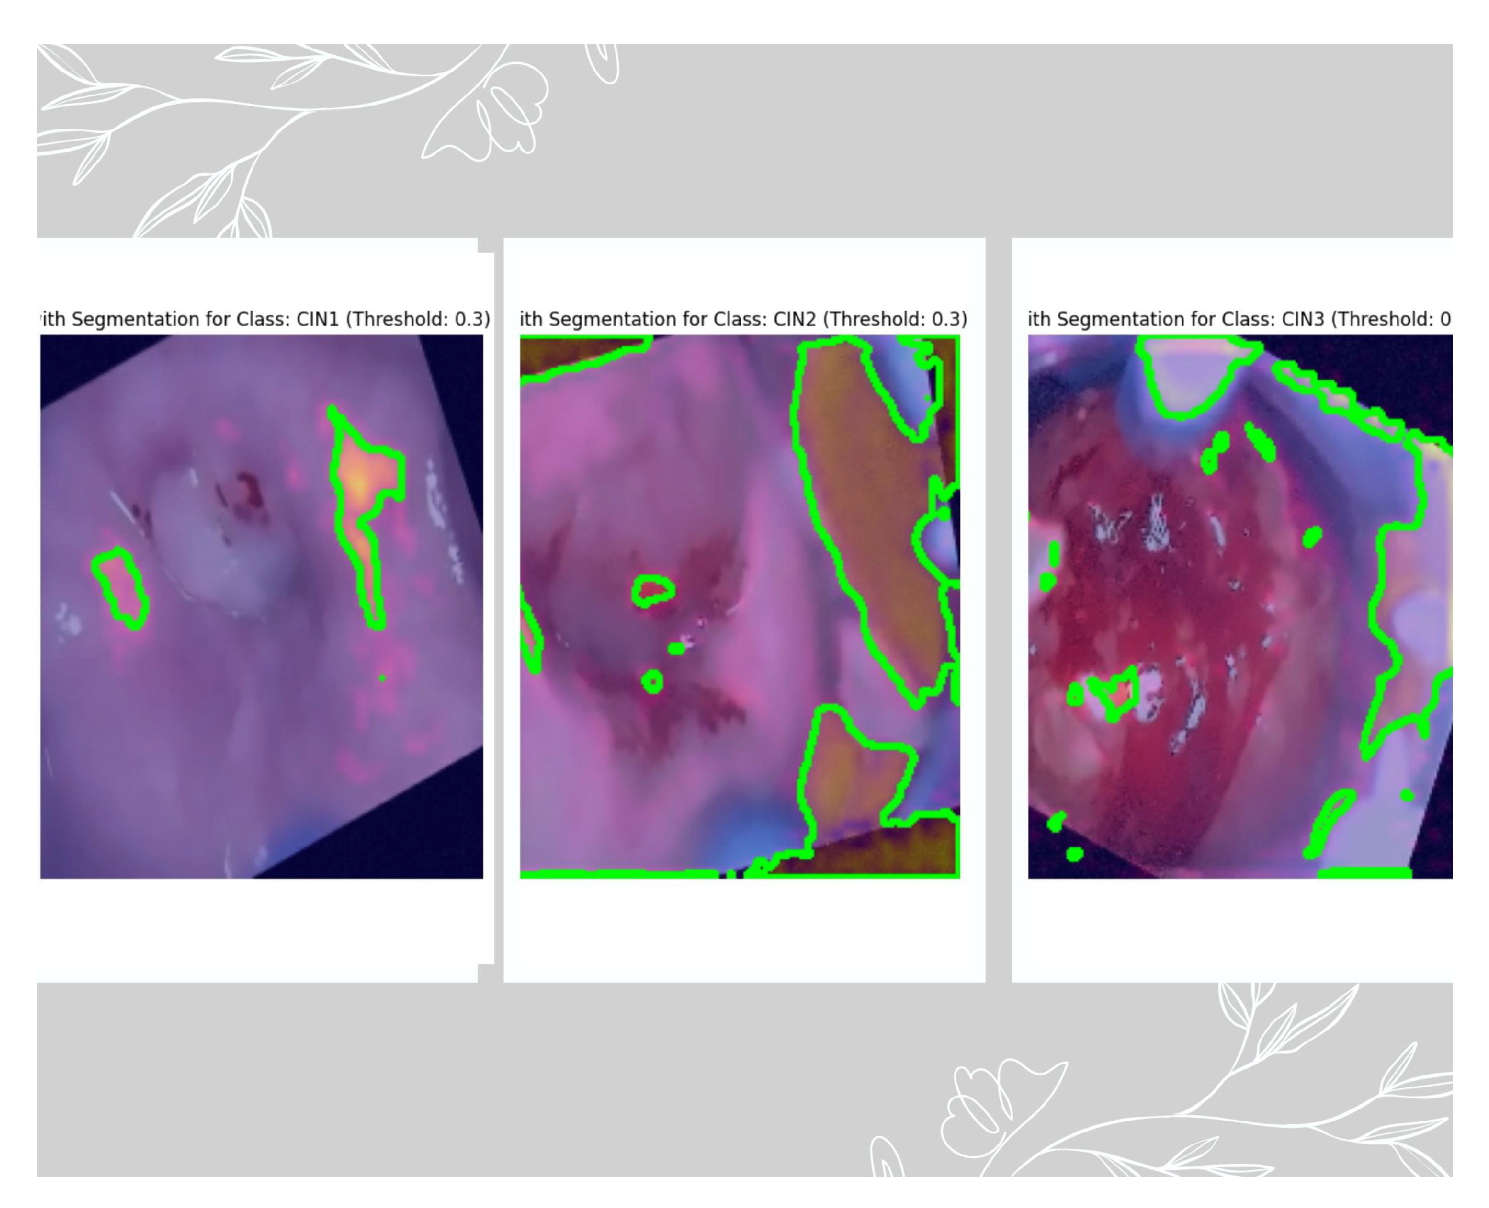

Purpose: Grad-CAM is used to interpret which parts of an input image are most important for a model’s prediction. In our case, Grad-CAM is applied to convolutional layer 5 (which captures high-level patterns) and combined with the gradients of the predicted class. The resulting heatmap overlays on the original colposcopy image, highlighting areas that influenced the model’s decision based on three different thresholds: 0.3, 0.5, and 0.6. These thresholds are empirically selected starting with common values like 0.3, selecting a midvalue of 0.5 and a little higher value of 0.6. Since the final validation accuracy is not very high, we fine-tuned these thresholds to generate a binary mask and to mark the ROI. This ROI is also confirmed by the medical practitioner. Equation 4 and equation 5 provides the mathematical basis.

This section provides the result of PCA, which was used to reduce the vector size from 4096 to 3, as seen in Figure 9. Grad-Cam was associated in the deepest layer (5th convolutional layer). We have used three thresholds to decide on the best feature extracted. As per the suggestion of the medical practitioner, we have selected the images based on threshold 0.3 as the best feature extractor for the three classes. Figure 10 depicts the mask with the ROI for the three classes based on the 0.3 threshold, where the first image is of CIN1, the second image is of CIN2, and the third image is of CIN3. Figure 11 shows the ROC-AUC curve of the three classes, and finally Figure 12 is the confusion matrix for the three classes on the validation dataset of 600 images.